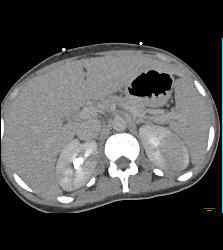

Normal Post Left Nephrectomy Bed